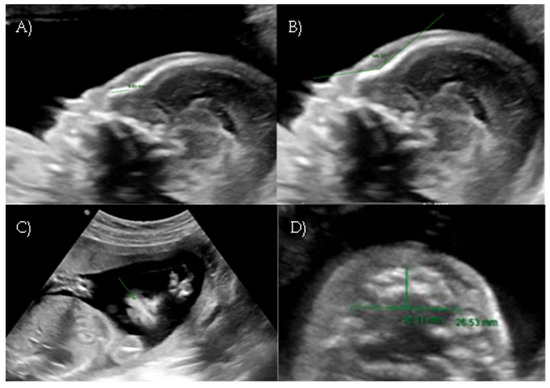

Her first-trimester combined screening for aneuploidies was low risk for trisomy 21, 18, and 13, and preterm preeclampsia. The nuchal translucency was within normal ranges (Figure 1A).

A detailed ultrasound scan was performed at 21 weeks and 1 day of gestation at our fetal medicine unit. Nasofrontal angle, nasal bone, and maxillary width were measured and compared to published references to unaffected fetuses at similar gestational ages [12,13]. Facial dysmorphism was further investigated by 3D scan (Figure 1B) through multiplanar mode and surface rendering, which allowed a more realistic representation of the fetal face, thus allowing characterization of the defect.

A flattened fetal facial profile with a nasal-frontal angle of 152.18° (cut-off: <143°, [14]), consistent with Binder-type maxillonasal dysplasia, was confirmed. To identify any other structural abnormalities, detailed examinations of the fetal anatomy and a fetal echocardiogram were conducted. No additional structural anomalies were identified (Figure 1C).

Figure 1. Case 1. (A) First-trimester 2D ultrasound Fetal profile. (B) Flat fetal profile, 21 weeks and 1 day, 3D reconstruction. (C) Nasal-frontal angle: 152.18°.